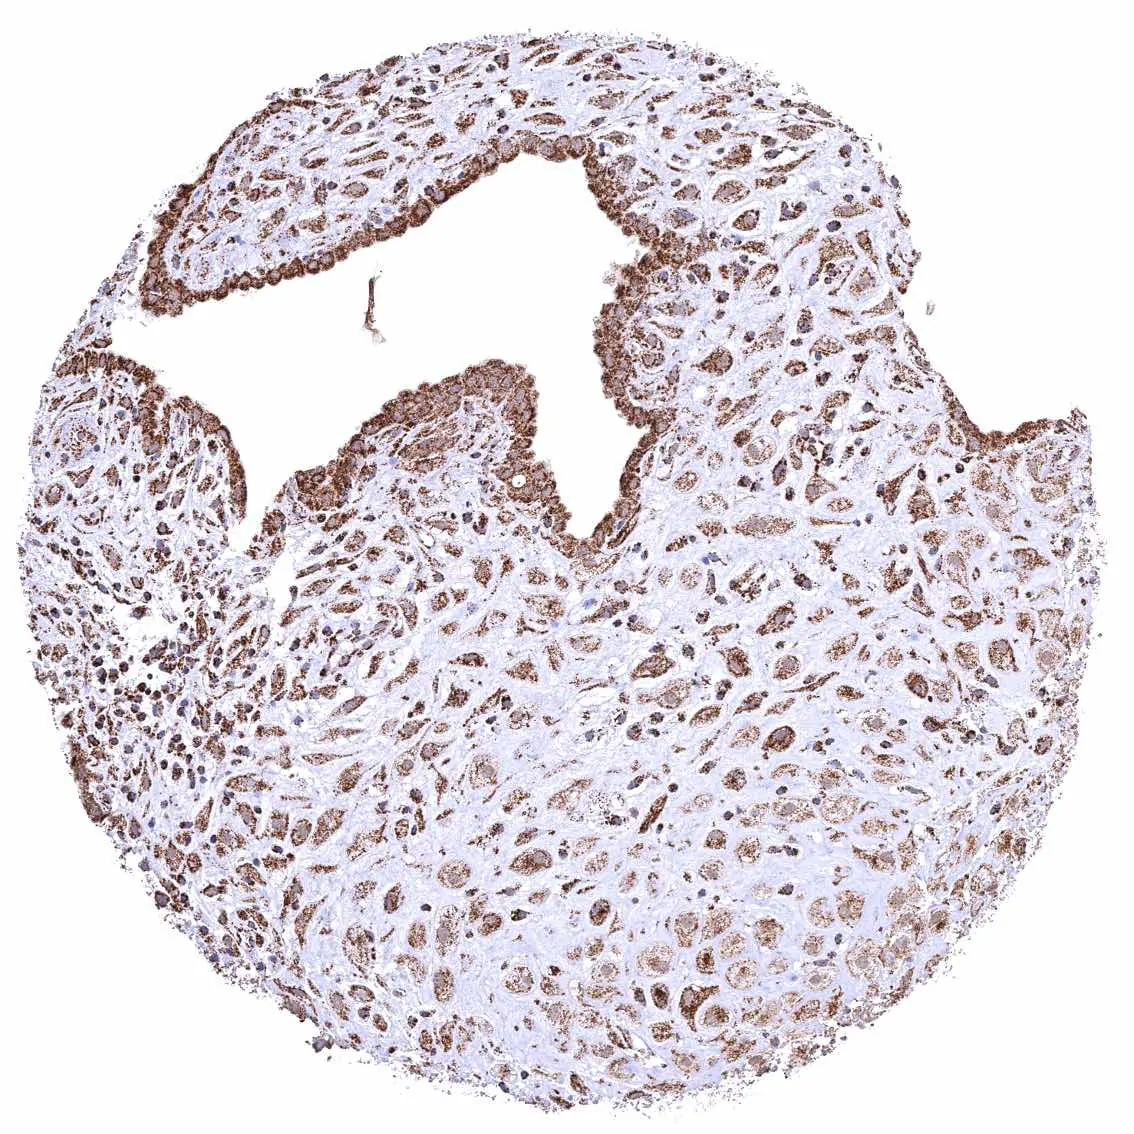

Uterus, ectocervix – Distinct granular, perinuclear, cytoplasmic ATP5J staining in all cell types. The staining is least intense in superficial cell layers of non-keratinizing squamous epithelium.